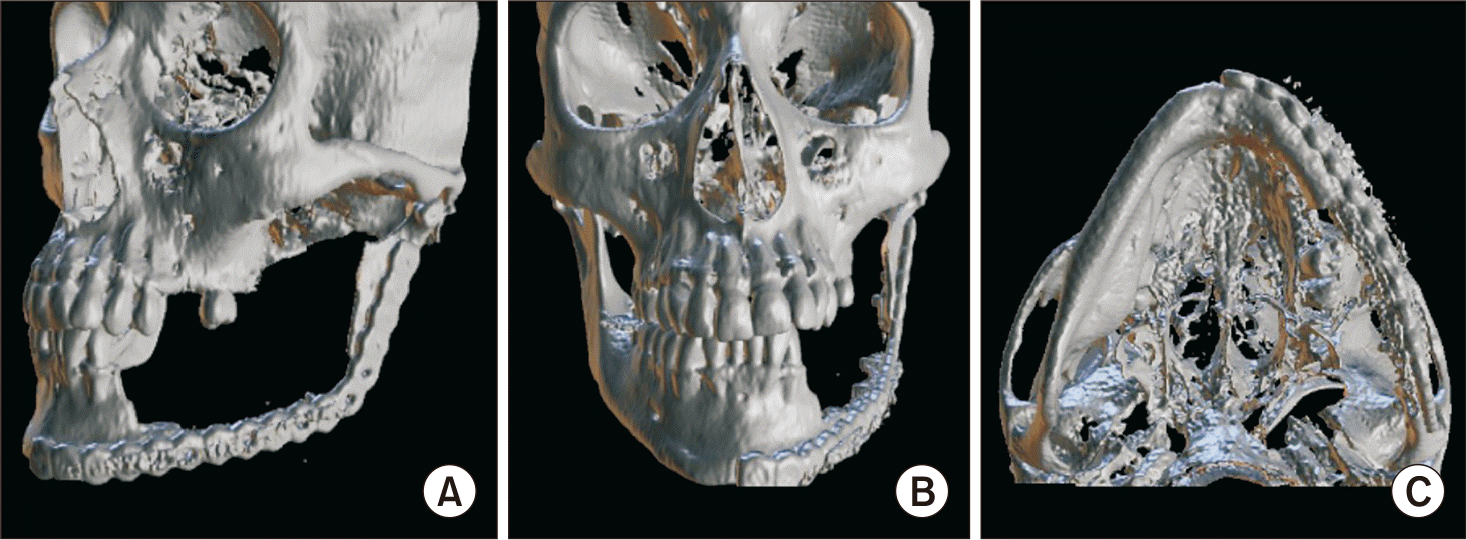

A 54-year-old female patient with a medical history of asthma and arterial hypertension, under treatment with prednisone, vitamin D, losartan, and primaquine. She had quit smoking 20 years prior. She was admitted to the maxillofacial surgery service due to an asymptomatic swelling in the mandibular region of the left body and angle, associated with teeth 3.6 and 3.7, which were displaced and mobile. Panoramic radiography revealed a multilocular radiolucent lesion expanding the cortical bone, with an approximate diameter of 8 cm.(Fig. 1) Biopsy confirmed the diagnosis of glandular odontogenic cyst. Surgery under general anesthesia was planned: excision of the lesion with a safety margin, reconstruction with an osteosynthesis system (OTS), and placement of an acrylic spacer to later evaluate the presence or absence of recurrence and to resolve the definitive reconstruction of the bone defect at a later stage.(Fig. 2)

Postoperative follow-up was scheduled at 1 week, 3 weeks, 2 months, 3 months, 6 months, and 1 year. The patient has currently completed 8 months of follow-up, with no signs of recurrence or wound dehiscence. Transient paresis of the frontal branch of the facial nerve was observed, with complete recovery at 3 months. Mild labial hypoesthesia persisted, likely related to the preoperative adhesion of the glandular odontogenic cyst to the inferior alveolar nerve. The aesthetic outcome was satisfactory, with minimal scarring and no need for drainage during the postoperative period.(Fig. 3)

Fig. 2

Postoperative three-dimensional reconstruction of left mandibular resection and positioning of osteosynthesis system with acrylic spacer. A. Lateral view. B. Frontal view. C. Caudal view.